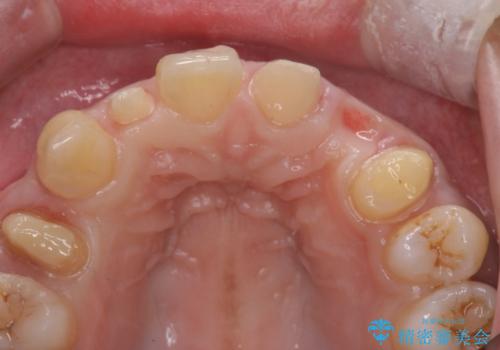

前歯の審美的なブリッジ (歯列矯正後)

- 歯列矯正後に前歯にブリッジを入れた方の経過です。

矯正治療で歯の位置を整えてからブリッジを入れると歯の幅を自由に設定できるため、左右対称にできます。結果矯正なしでいきなりセラミックにする場合と異なり、無理に角度を変えたりする必要がなく、神経をなるべく温存したまま審美的なセラミック治療が行えます。